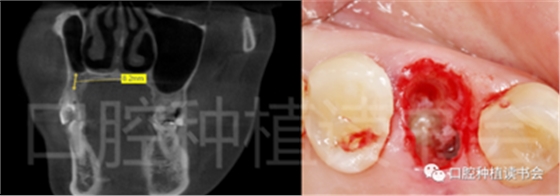

另外,牙根的長(zhǎng)度(根分叉到根尖的長(zhǎng)度)將決定安全種植的骨高度或深度,應(yīng)避免根尖以外的解剖“危險(xiǎn)區(qū)”(例如,下牙槽神經(jīng)、上頜竇,圖11)。

圖11 擬行即刻種植的位點(diǎn)術(shù)前應(yīng)CBCT檢查

根分叉距離下頜神經(jīng)管或上頜竇的距離。

術(shù)前CBCT(美亞光電)檢查:47根分叉下方骨高度及骨寬度滿足即刻種植要求(圖13)。

圖13 47根分叉區(qū)骨寬度及骨高度(與下頜神經(jīng)管之間的距離)滿足即刻種植要求。

5.3.6 術(shù)后即刻CBCT(美亞光電)檢查種植體軸向及深度良好(圖19)。

圖19 術(shù)后即刻CBCT確認(rèn)種植體頰、

舌側(cè)骨板完整,并保持了足夠的厚度。

5.4.4 種植冠封閉螺絲孔后,調(diào)合,拋光,完成最終修復(fù)(圖27);戴牙前CBCT顯示:種植體頰側(cè)骨板厚度為2.88mm;47種植冠獲得了良好的穿齦輪廓,并維持了正常的頰側(cè)牙弓輪廓。